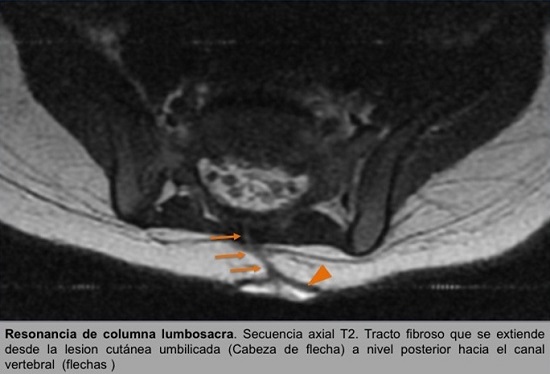

• RM de columna lumbosacra: hallazgos compatibles con disrafismo espinal oculto, seno dérmico con obliteración fibrosa de la comunicación con canal vertebral en paciente con médula anclada (cono medular a la altura de cuerpo vertebral L3) que asocia dilatación quística del filum terminal y lipomatosis.